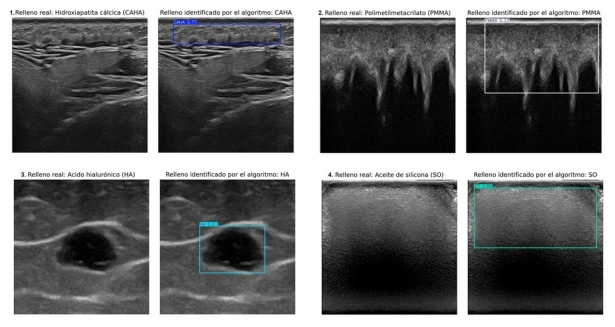

Universidad de Granada y de Chile desarrollan IA para identificar rellenos estéticos en ecografías

El sistema automatiza el diagnóstico en tratamientos cosméticos, mejorando la precisión y facilitando la atención clínica